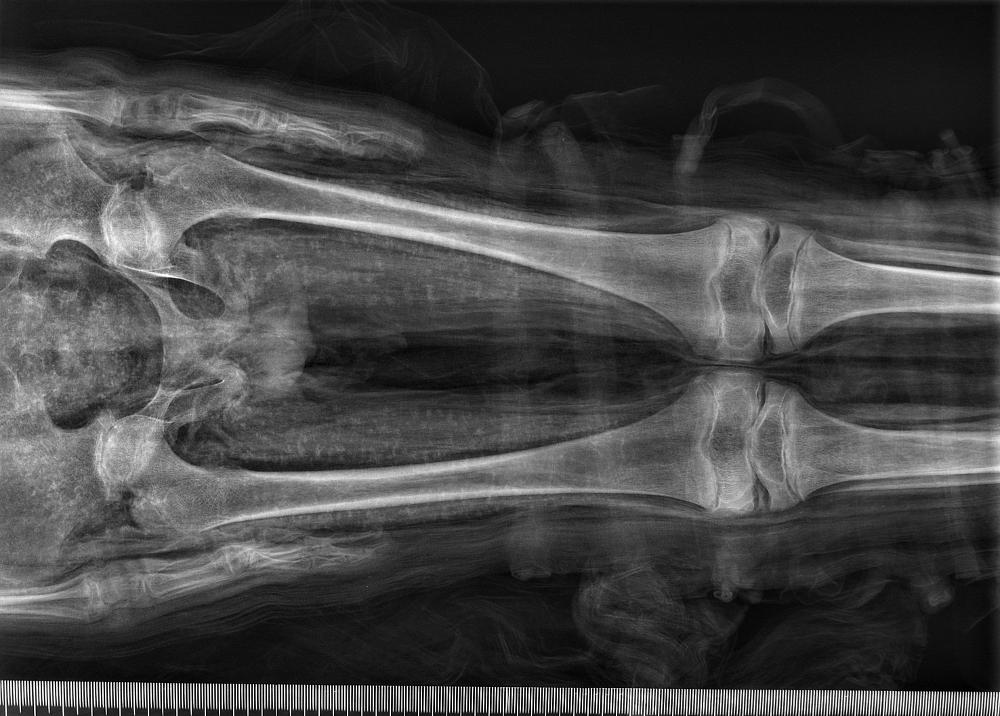

mummy, boy, human remains

- The mummy of a small boy.